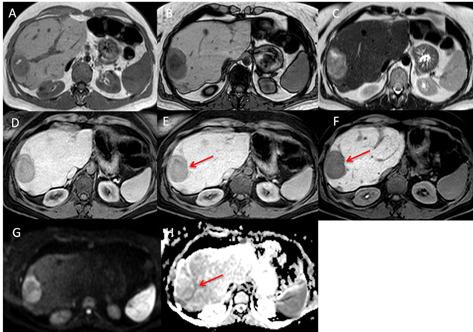

On computed tomography (CT) and magnetic resonance imaging (MRI), hepatocellular tumors are characterized based on typical imaging findings. However, hepatocellular adenoma, focal nodular hyperplasia, and hepatocellular carcinoma can show uncommon appearances at CT and MRI, which may lead to diagnostic challenges. When assessing focal hepatic lesions, radiologists need to be aware of these atypical imaging findings to avoid misdiagnoses that can alter the management plan. The purpose of this review is to illustrate a variety of pitfalls and atypical features of hepatocellular tumors that can lead to misinterpretations providing specific clues to the correct diagnoses.

在计算机断层扫描(CT)和磁共振成像(MRI)上,根据典型的影像学表现可对肝细胞肿瘤进行特征描述。然而,肝细胞腺瘤、局灶性结节性增生和肝细胞癌在 CT 和 MRI 上可能会出现不常见的表现,这可能导致诊断上的挑战。在评估局灶性肝病变时,放射科医生需要注意这些非典型的影像学表现,以避免误诊,误诊可能会改变治疗计划。本文旨在说明导致误诊的肝细胞肿瘤的各种陷阱和非典型特征,并提供正确诊断的具体线索。